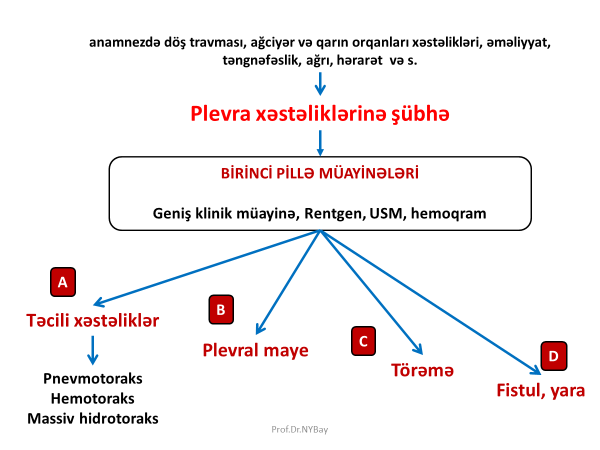

Şübhə

Anamnezdə döş travması, ağciyər, divararalığı və qarın orqanları xəstəlikləri, əməliyyatları, müdaxilələr (damarların kateterizasiyası, intubasiya və s), təngnəfəslik, ağrı, hərarət, və s. plevra xəstəliklərinə şübhə yaradır.

Şəkil 1. Birinci pillə müayinələrin nəticələri

Birinci pillə

Birinci pillə müayinələrdə məqsəd plevrada təcili cərrahi xəstəliyin olub-olmamasını, maye, kütlə və fistula kimi üzvi dəyişikliklərin olub-olmamasını müəyyənləşdirməkdir. Bunun üçün hərtərəfli klinik müayinə, hemoqram, Rentgen və USM edilir. Birinci pillə müayinələrdən bir neçə nəticə ortaya çıxa bilər (Şəkil 1):

- Təcili xəstəliklər

- Plevral maye

- Plevrada törəmə

- Döş divarında fistula

Təcili xəstəliklərdə diaqnostika